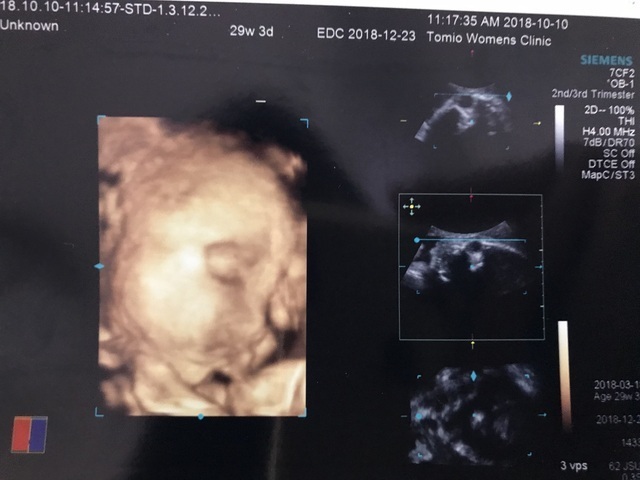

29週3日(29w3d・男の子)|519かおり さん(29歳)

エコー写真撮影時のエピソード:

初めて4Dをしてもらって赤ちゃんがより分かり、すごくすごくうれしかったのを覚えてます。

妊娠中は私の体調はあまりよくなかったのですが、赤ちゃんが頑張ってるから私も頑張ろうと元気をもらったなぁと思い出しました。パパや家族がすごく喜んでました。